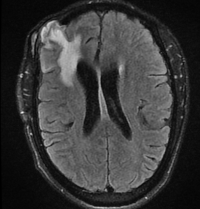

We report the case of a 29-year-old Nigerian male with end-stage kidney disease on dialysis who presented with headaches, fever, generalised seizures, and left-side emiplegia. His brain MRI revealed a contrast-enhancing right frontotemporal mass lesion with surrounding oedema and midline shift, initially suggestive of a cerebral abscess.

Empirical treatment with antibiotics, steroids, and anticonvulsants provided partial relief. Surgical intervention via craniotomy and partial resection revealed a vascular, greyish-yellow mass. Histopathology confirmed Schistosoma eggs surrounded by granulomatous inflammation, establishing a diagnosis of cerebral schistosomiasis.

The patient was treated with praziquantel and dexamethasone, and levetiracetam, leading to complete resolution of neurological symptoms and seizure control. Follow-up imaging showed significant lesion regression.